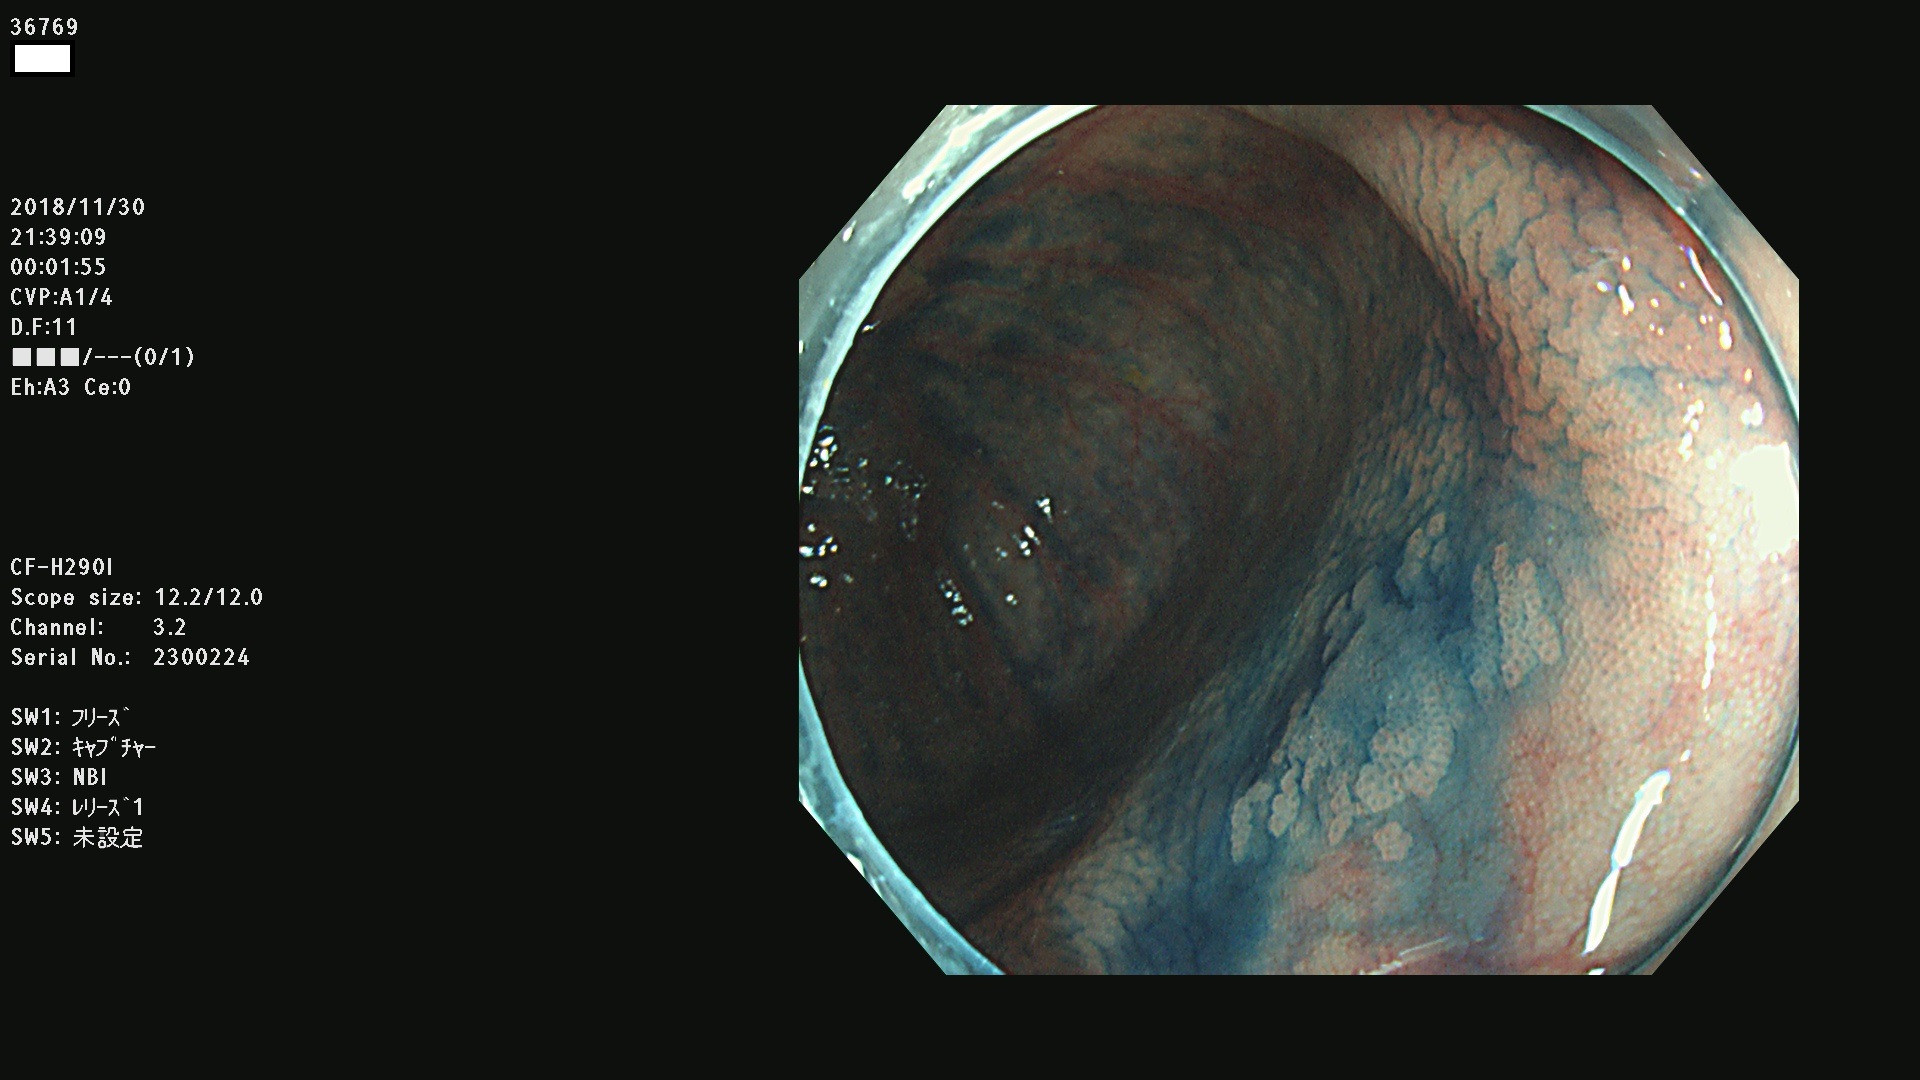

発見困難で危険性の高い平坦型病変(上記100名より抽出)